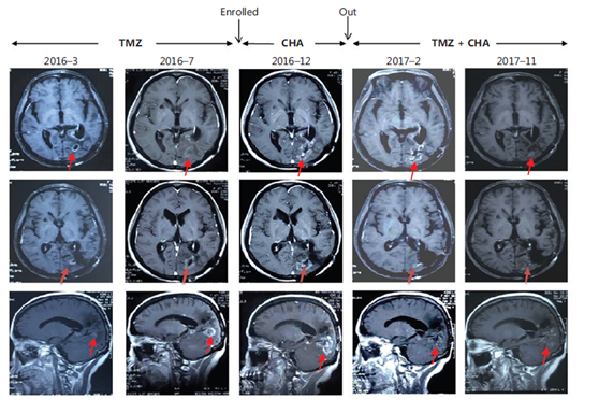

治療惡性腦膠質瘤Ⅰ期臨床研究特殊病例分析:注射用綠原酸有效延長受試者生存期,并能一定程度解除受試者對替莫唑胺的耐藥現象

受試者入組時替莫唑胺耐藥且疾病進展;

使用注射用綠原酸后病情得到有效控制,出組后再次使用替莫唑胺治療,MRI結果顯示替莫唑胺再次起效。

患者采用替莫唑胺與注射用綠原酸交替使用、聯合治療的方案,顱內病灶目前已完全消失,從確診至今,生存期已超過13年。

病例圖片來源 Kang, Z. , Li, S. , Kang, X. , Deng, J. , Yang, H. , & Cheni, F. , et al. (2023). Phase Ⅰ study of chlorogenic acid injection for recurrent high-grade glioma with long-term follow-up. 癌癥生物學與醫(yī)學:英文版, 20(6), 465-476.